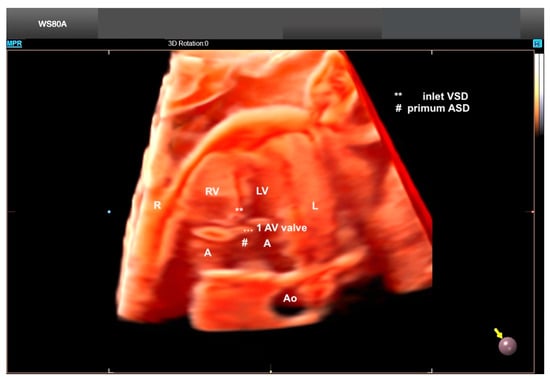

Figure 10.

Crystal Vue and Realistic Vue in a case of unbalanced AV septal defect and left atrial isomerism. Note the small LV. Virtual light source position, 10 o’clock. Rotation, 0°. LV: left ventricle; A: atrium (left-sided morphological atrium); RV: right ventricle; AV: atrioventricular; Ao: aorta; R: right side of the fetus; L: left side of the fetus; VSD: ventricular septal defect; ASD: atrial septal defect.